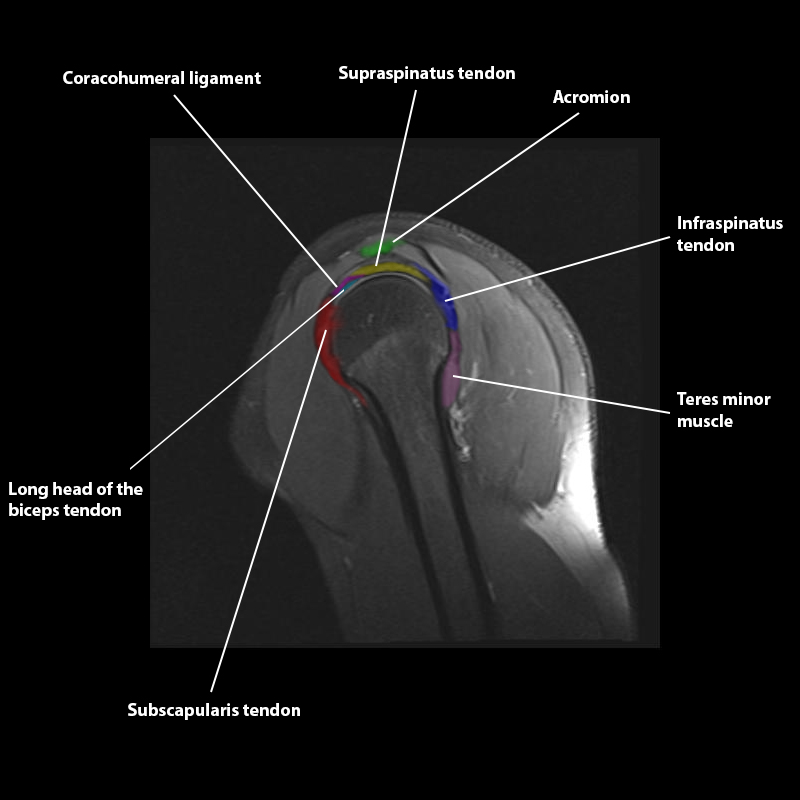

Shoulder MRI Anatomy